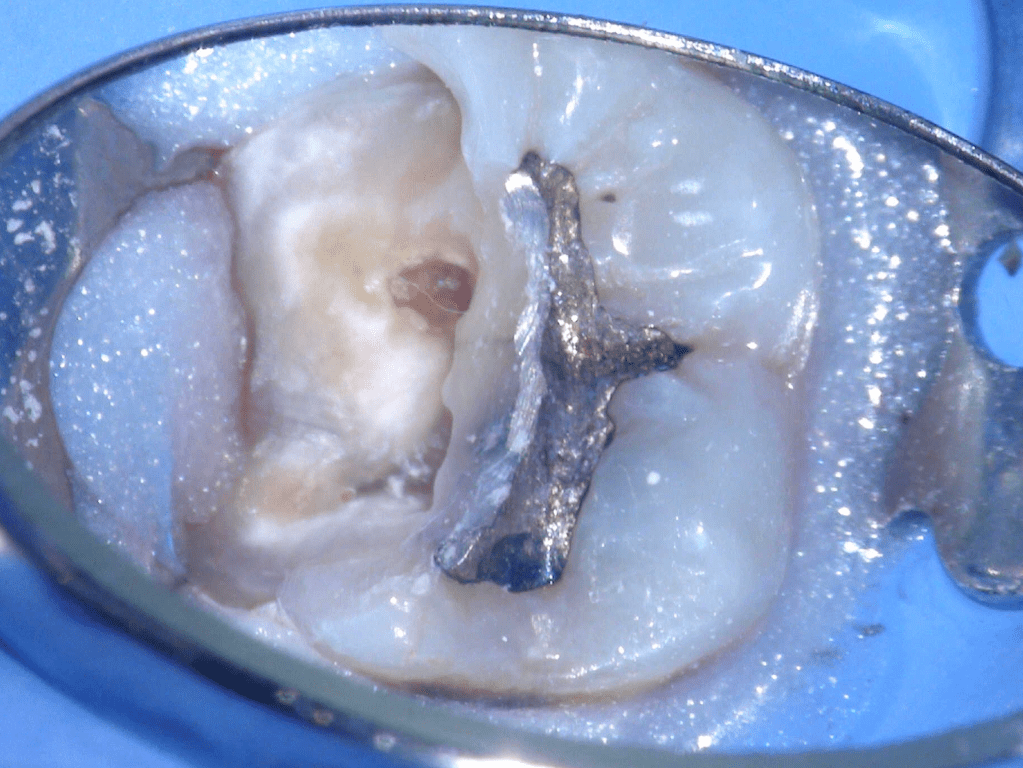

Fisura, remoción amalgama para explorar